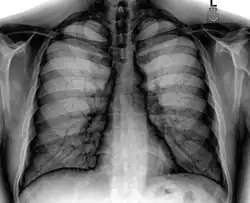

A chest radiograph, chest X-ray (CXR), or chest film is a projection radiograph of the chest used to diagnose conditions affecting the chest, its contents, and nearby structures. Chest radiographs are the most common film taken in medicine.

Like all methods of radiography, chest radiography employs ionizing radiation in the form of X-rays to generate images of the chest. The mean radiation dose to an adult from a chest radiograph is around 0.02 mSv (2 mrem) for a front view (PA, or posteroanterior) and 0.08 mSv (8 mrem) for a side view (LL, or latero-lateral).[1] Together, this corresponds to a background radiation equivalent time of about 10 days.[2]

Chest radiographs are used to diagnose many conditions involving the chest wall, including its bones, and also structures contained within the thoracic cavity including the lungs, heart, and great vessels. Pneumonia and congestive heart failure are very commonly diagnosed by chest radiograph. Chest radiographs are also used to screen for job-related lung disease in industries such as mining where workers are exposed to dust.[3]